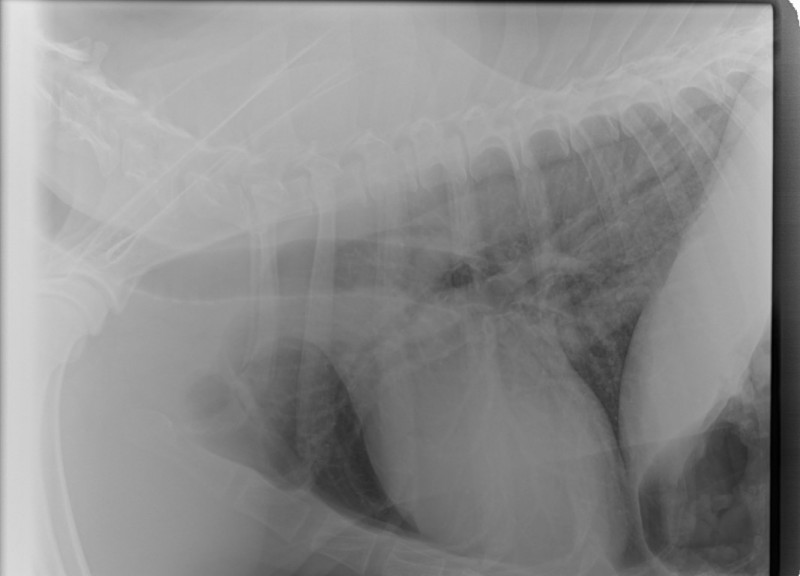

The Vet and I discussed x-days of her chest/lungs for her Vet was not comfortable with the looks of that remaining mass. frown emoticon Nor, with this sudden huge weight loss.

I was so worried gowning up to help with the x-Rays……

The good news is that her lungs, at this time have shown no signs of anything that has metastisized.

I have her x-Rays to post on her blog, photo’s of her masses and, one of a recovering sweet BHRR’s Ani from sedation. She also received a lovely mani/pedi!